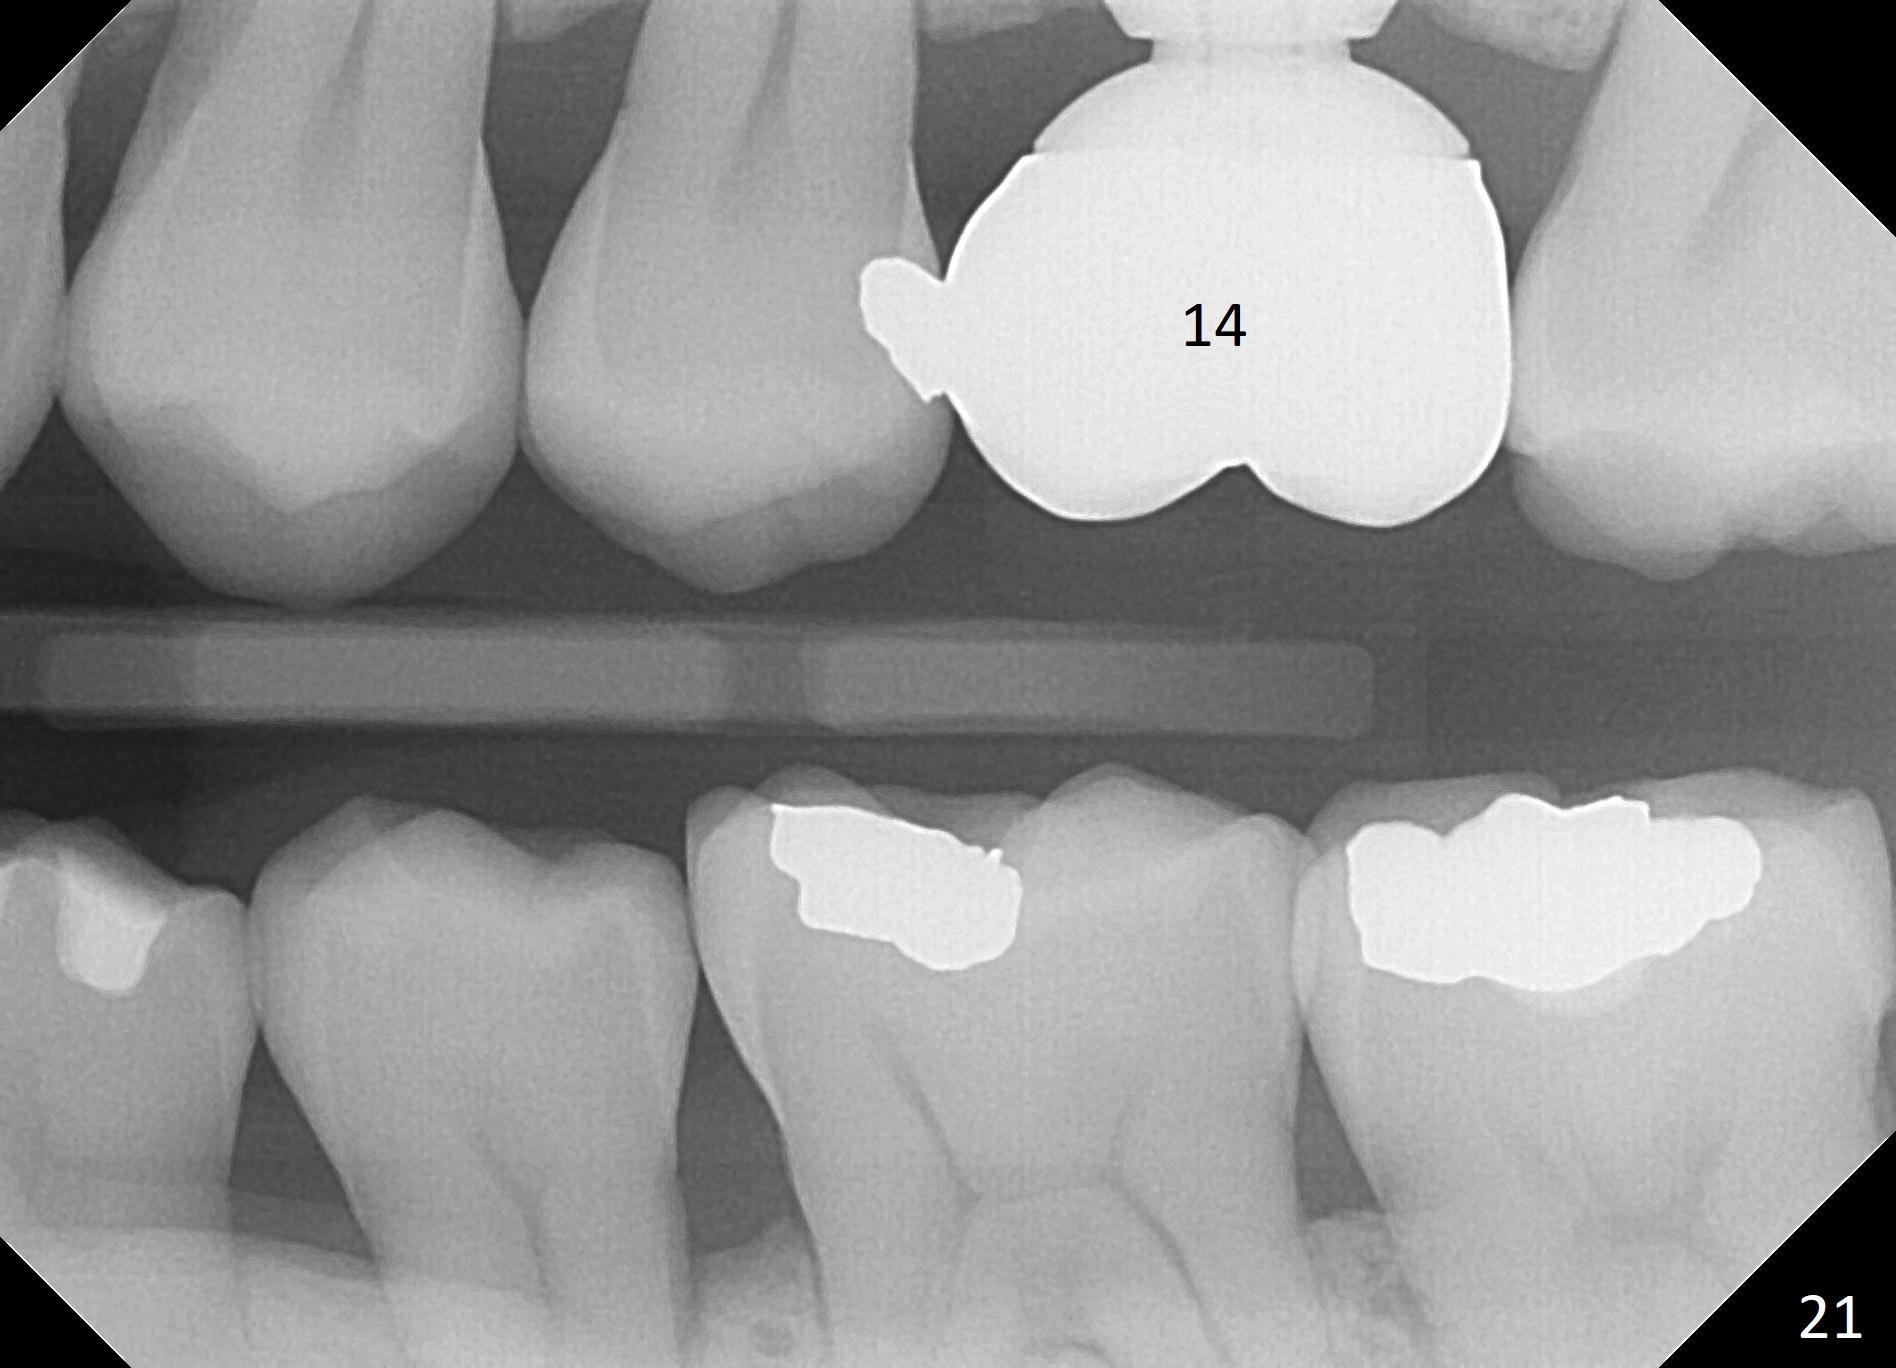

A 45-year-old man has lost the tooth #14 for a while (Fig.1); bone height is 5.4 mm. An extra wide and short implant is planned. Torus palatinus is large, suggesting that bone density should be high. A 6 mm tissue punch is chosen, but it is placed more palatal. If it were placed in the middle of the ridge, there would be no buccal keratinized gingiva (incision may avoid this issue). Additionally, the buccal portion of punch is made incomplete so that there is pedicle on the buccal side when the flap is raised (Fig.4,8: F). It is expected that the excess portion of keratinized tissue will form thick gingiva buccally. Osteotomy proves that bone is dense (Fig.2 (4.5x11 mm tap). Typical sinus lift is finished with placement of 6.4x6 mm (extra wide) bone-level implant (Fig.3, >55 Ncm). Following further torque, Fig.4 shows that the implant (I) is sub-gingival (<). Bitewings are taken to confirm that the implant plateau is at the crestal level (Fig.5,6 ^). PA shows sinus lift (Fig.7 *). The lingual aspect of the implant and healing abutment (H) is further bone grafted and covered by collagen dressing (Fig.8 *). The wound is protected with perio dressing. When the latter dislodges 7 days postop, the collagen dressing and bone graft are lost as well (Fig.10), while the buccal flap remains vital (Fig.9). The lingual exposed plateau should be able to heal normal. The collagen dressing should have been fixed in place by suture or as simple as a dental floss. There is mild nasal hemorrhage 1-2 days postop, possibly related to sinus membrane perforation and inability of Collagen Dressing to cover the perforation and contain the bone graft. When the patient returns for #9 implant placement in 3 weeks postop, the buccal flap reduces in size (Fig.11 *), while the palatal wound has healed with minimal exposure of the implant (Fig.12). Sinus graft remains in place 3 months postop (Fig.13); the buccal flap appears to have incorporated into a part of the gingiva (Fig.14). The bone density of the sinus lift appears to increase 10 days later when an abutment is placed (Fig.15 *). Although oral hygiene is pristine, there is apparent crestal bone resorption 12 months (Fig.16) and 20 months (Fig.17) post cementation, probably due to unfavorable crown/implant ratio and bruxism as well as pre-implantation bone loss (Fig.18,19). In contrast, an immediate implant in the same patient avoids pre- or post-implantation bone loss. In fact both the soft (Fig.20) and hard (Fig.21) tissues remain healthy 2 years 8 months post cementation. The sinus lift remains 3 years 8 months post cementation (Fig.22), while the crestal bone loss persists. The patients keeps complains of food impaction distal associated with bad smell 4 years 1 month post cementation. In fact the distal proximal contact is within normal limit. The bad smell is probably due to crestal bone loss (Fig.23 (pan), 24 (CT) *) and periimplantitis. Bone graft, PRF and Cytoplast membrane will be needed and fixed in place with long healing screw. When the patient returns for crown redo, he also reveals floss related gingival hemorrhage. There is pain associated with palatal sulcus probing with light gingiva erythema. Review of CT coronal section shows possible palatal (Fig.25 P) bone loss (*).